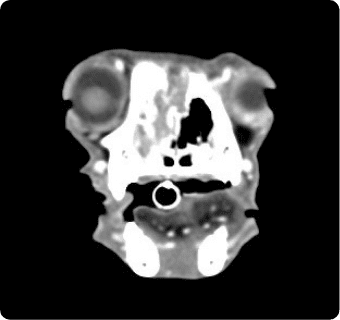

빠른 촬영속도를 통해 마취시간을 최소화 하며, 선명한 3차원 영상을 구현합니다.

종양, 전이평가, 선천적 혈관 기형 등 여러 질환의 조기 발견 및 환자상태를 평가합니다.

이도(외이염, 중이염), 뇌수두증, 비염, 치과질환, 두경부 종양, 비강종양, 침샘질환